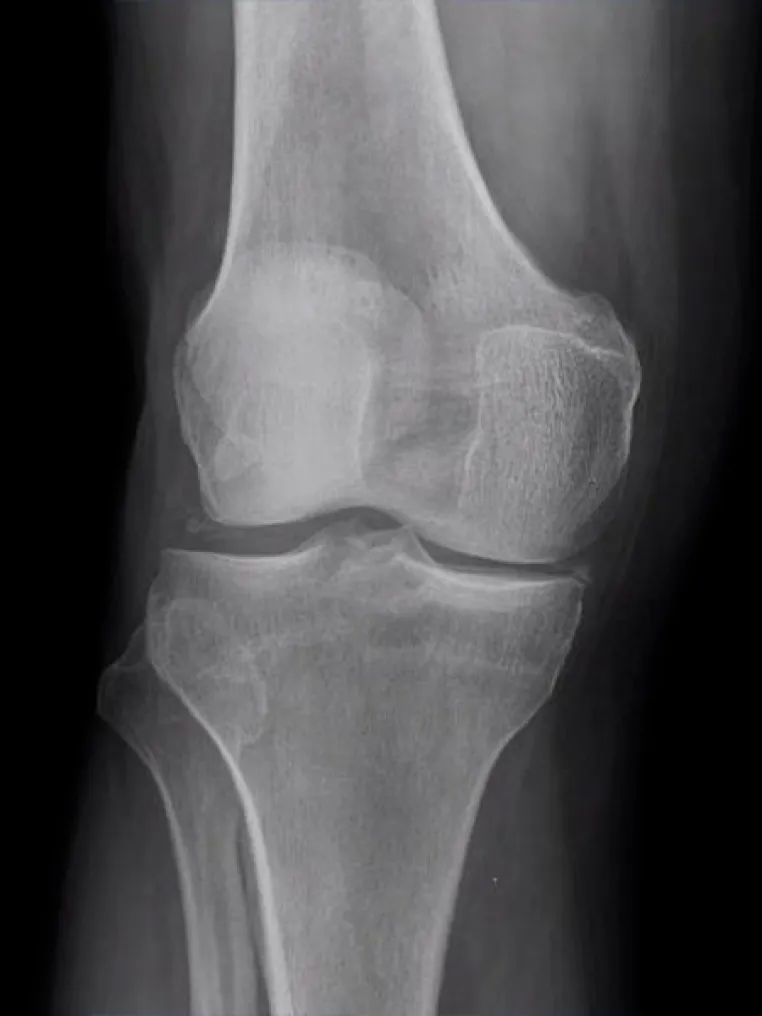

La Unidad especializada del aparato locomotor de IMED Hospitales se especializa en el diagnóstico y tratamiento de patologías musculoesqueléticas mediante un enfoque multidisciplinar y el uso de técnicas mínimamente invasivas, como la cirugía artroscópica y la medicina regenerativa. Estas técnicas avanzadas permiten acortar los tiempos de recuperación y mejorar la calidad de vida de nuestros pacientes.

Nuestro equipo de especialistas aplica tecnologías de vanguardia como el diagnóstico por imagen avanzado (resonancia magnética de 3 teslas, TAC multicorte) y tratamientos innovadores como el plasma rico en plaquetas y prótesis de última generación. Además, contamos con una amplia experiencia en medicina deportiva y cirugía protésica, ofreciendo soluciones adaptadas tanto a deportistas como a pacientes con desgaste articular.